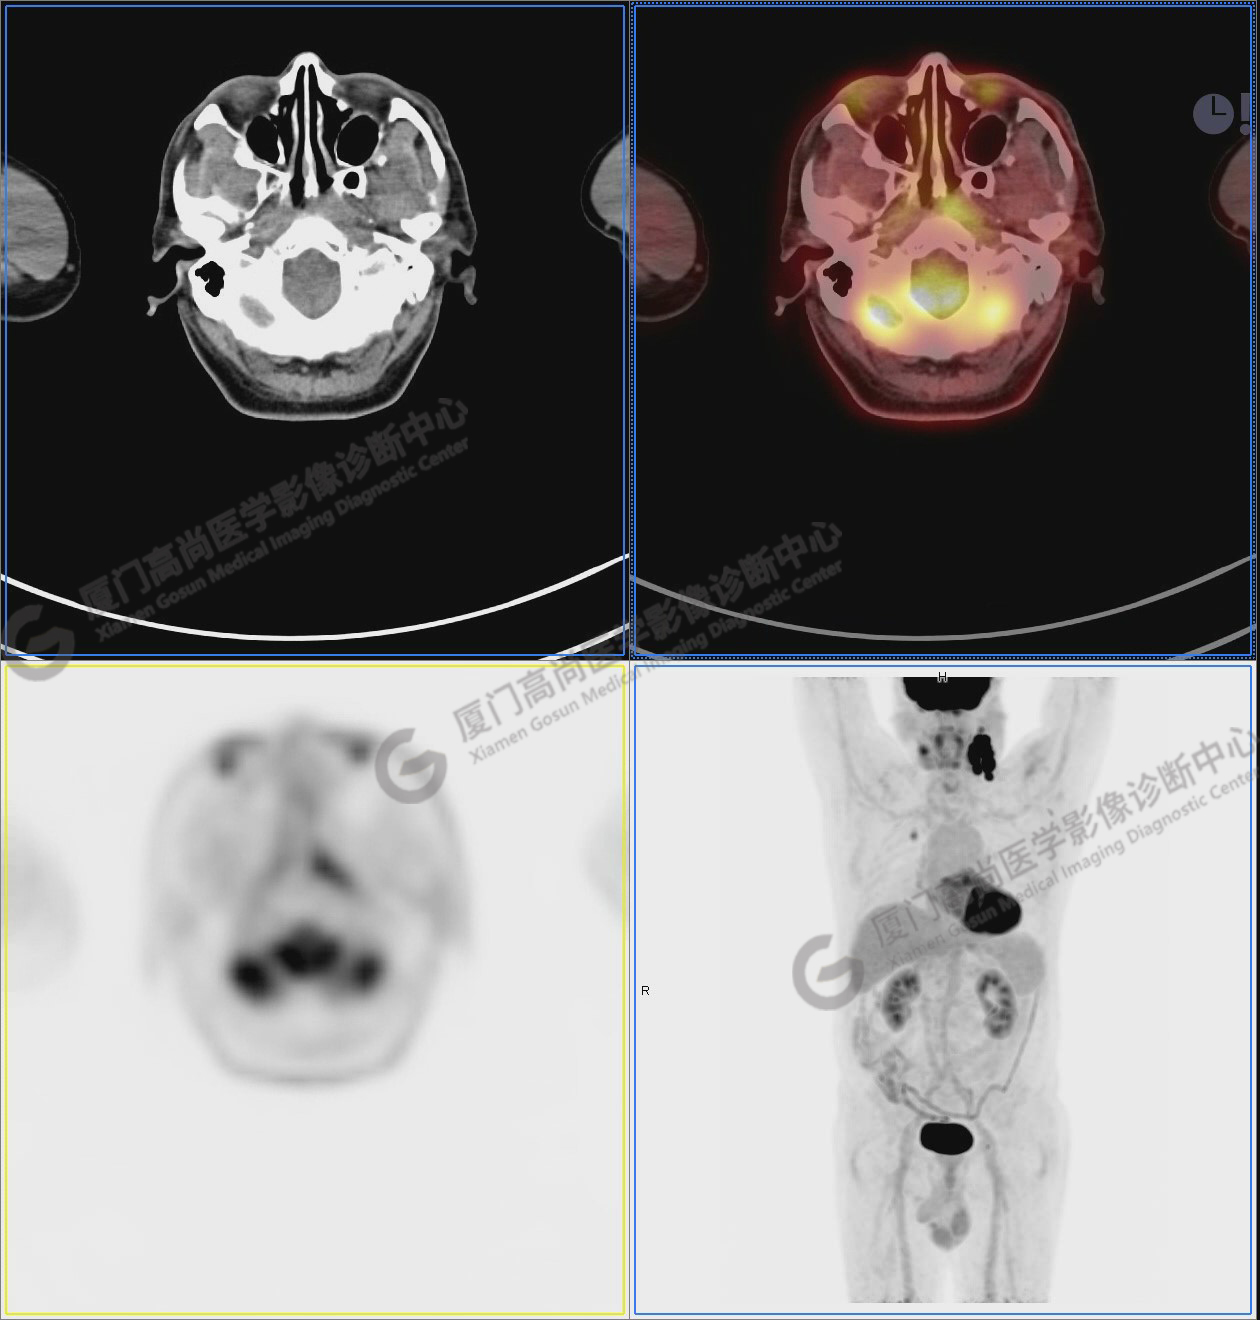

圖6-9:鼻咽左側(cè)壁增厚,代謝異常增高,考慮為鼻咽癌